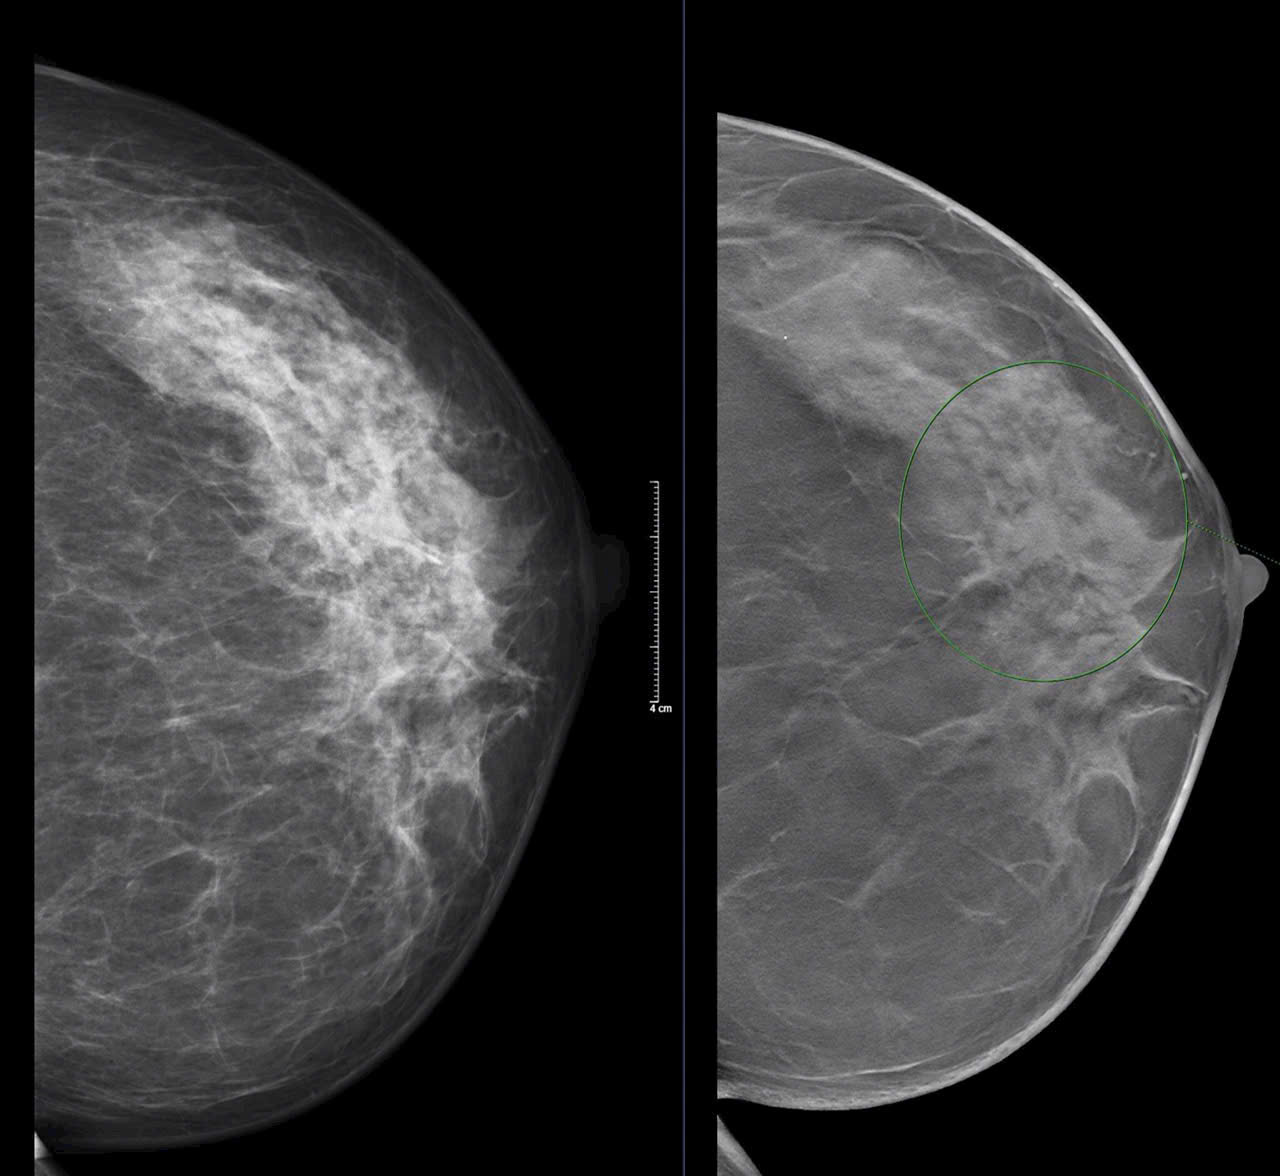

Những Hiểu Lầm Về Phương Pháp Tầm Soát Các Bệnh Lý Tuyến Vú

Tầm soát các bệnh lý tuyến vú đóng vai trò quan trọng trong việc phát hiện sớm các bệnh lý về tuyến vú và ung thư, giúp cải thiện hiệu quả điều...